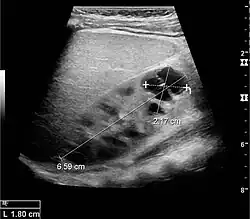

Cortical thickness should be estimated from the base of the pyramid and is generally 7–10 mm. If the pyramids are difficult to differentiate, the parenchymal thickness can be measured instead and should be 15–20 mm (Figure 3). The echogenicity of the cortex decreases with age and is less echogenic than or equal to the liver and spleen at the same depth in individuals older than six months. In neonates and children up to six months of age, the cortex is more echogenic than the liver and spleen when compared at the same depth.[1]

Figure 3. Measures of the kidney. L = length. P = parenchymal thickness. C = cortical thickness.[1]